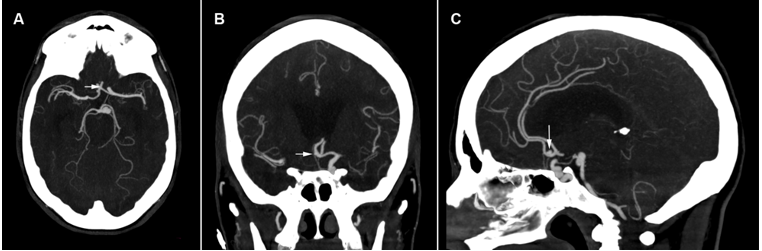

As a part of our research routine, we realized a retrospective CTA-based 3D modeling using the « 3D slicer » software. The 3D model’s results met the surgical findings concerning the paraclinoid and posterior aneurysm (Figure 5). In addition, it incidentally revealed a 5.2mm ACOA aneurysm (Figure 6). After discussion with neurosurgeons, the rebleeding was attributed to the rupture of the ACOA aneurysm.

The incidental diagnosis of the ACOA aneurysm

The 3D slicer modeling incidentally revealed an ACOA aneurysm. When we revised the CTA and 3D CTA images, a little outpouching from the ACOA drew our attention (Figure 4, Figure 7, Figure 8). Regarding the anatomical layout of the ACOA complex, it was difficult to determine whether the lesion was an aneurysm or to decide on its origin. Given the urgency and within the limits of the CTA images, we believe that the radiologist and neurosurgeons did not analyze the ACOA complex properly. It is probably why they missed the diagnosis. In the 3D slicer modeling, we used an uncommon view angle to see the aneurysm. In addition, with the automatic segmentation, we got a good-quality 3D model in a few minutes. Thus, 3D slicer modeling is adaptable to urgency. Neurosurgeons were surprised by the quality of the 3D model since it met the surgical findings and added new features about the ACOA aneurysm. They believed that, with this method, they would have optimized the therapeutic choice and avoided the tragedy. Indeed, if 3D modeling had been done before surgery, the ACOA aneurysm would have been diagnosed and treated. The patient would have less risk of rebleeding.

Figure 7.Sagittal, axial, and coronal brain CTA images: the white arrow indicates a suspicious lesion of the anterior communicating artery.

Figure 8.3D brain CTA images: the white arrow indicates a suspicious outpouching from the anterior communicating artery.